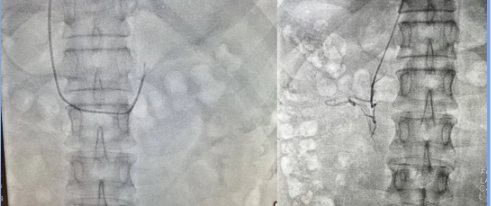

此外,在全国高血压日前夕,萍乡市人民医院心血管病医院在国内知名心脏病专家、心血管病医院洪浪院长指导下已连续开展了数例经导管分侧肾上腺静脉术(AVS),为原发性醛固酮增多症高血压患者分型及诊治提供精准依据,目前均取得良好的疗效,为萍城百姓带来了福音。